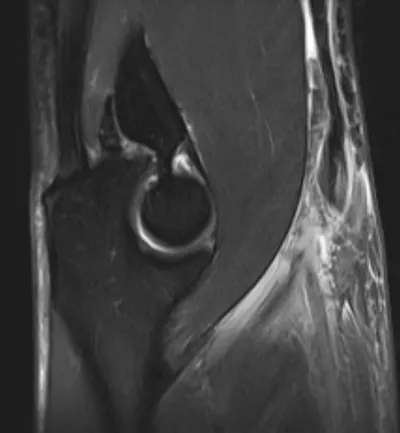

Synovial Osteochondromatosis of Elbow

Elbow

4/10/2026